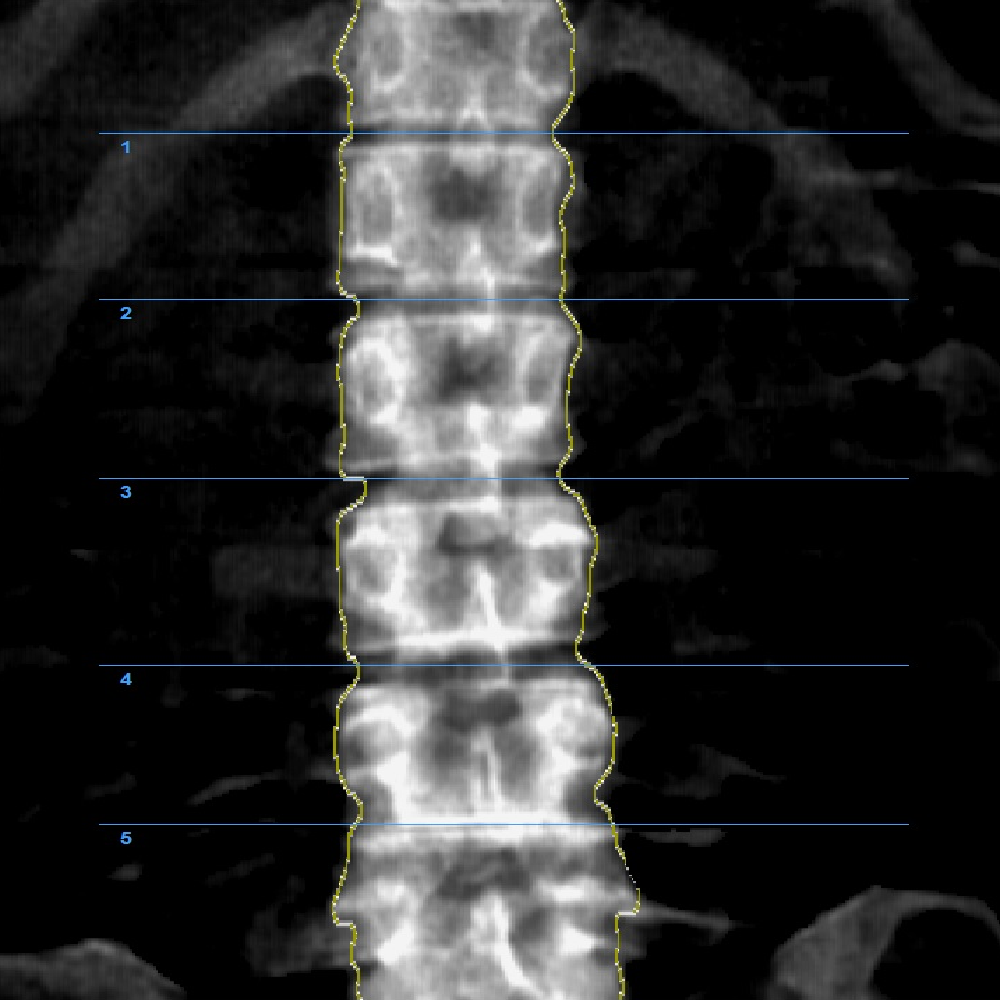

64 channel DXA Bone Densitometry

InAlyzer AIR uses 64 ch dual energy x-ray detector based on Fan Beam technology and obtains 64 rows of data per one x-ray irradiation, enabling acquisition of data of higher resolution in a shorter time, unlike pencil beam system that obtains 1 row of data per one x ray irradiation. Also the reliability and durability was enhanced by using an x ray generator that does not require fast switching between high energy and low energy, and the x ray detector that acquires high resolution data of high energy and low energy independently provides high-quality images.

By applying the energy-fixed x-ray generator, we minimized the failure rate, while the energy-independent high-resolution detector provides fast high resolution results.

3. Powerful & user-friendly Interface

In addition to high resolution images, it provides various image-processing tools and the user-friendly ROI (Region Of Interest) enables convenient and accurate use of the analysis. Also, the self-diagnosis allows the equipment to maintain its performance and produce precise results.